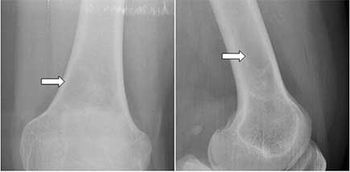

Case History: 20-year-old female with mild pain in left knee joint area, no history of injury and laboratory test was normal for inflammation or rheumatoid.